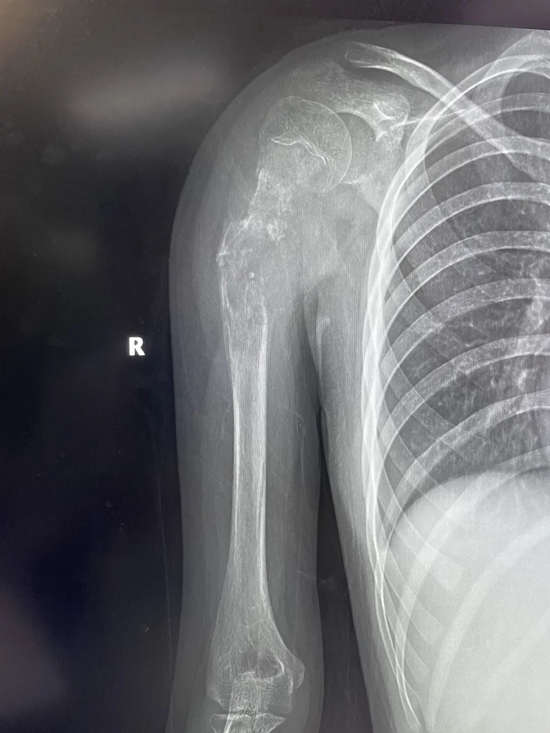

小欣(化名)因右肱骨中上段肿瘤,饱受疾病折磨,几经辗转后来到西安市红会医院就医,活检确诊为右肱骨中上段骨肉瘤。

骨病肿瘤科杨团民主任介绍,骨肉瘤是一种好发于儿童长骨的骨端高度恶性的原发性肿瘤,治疗原则为手术结合化疗、放疗综合治疗。由于肿瘤范围较大没有生物重建可能,也没有相关肿瘤假体,保肢难度很大,一直是业内难题,所以普遍选择截肢。

针对小欣的具体病情,骨病肿瘤科杨团民主任带领团队成员王志酬、黄桂林、邵宇雄、李争争主治医师等人,经过认真病例讨论,决定新辅助化疗后,手术切除右肱骨骨肿瘤。发挥3D打印在骨科领域优势,设计个体化3D打印肱骨上段钛合金假体,结合人工肩关节技术,保留部分正常骨、患肢长度,可实现肱骨重建。